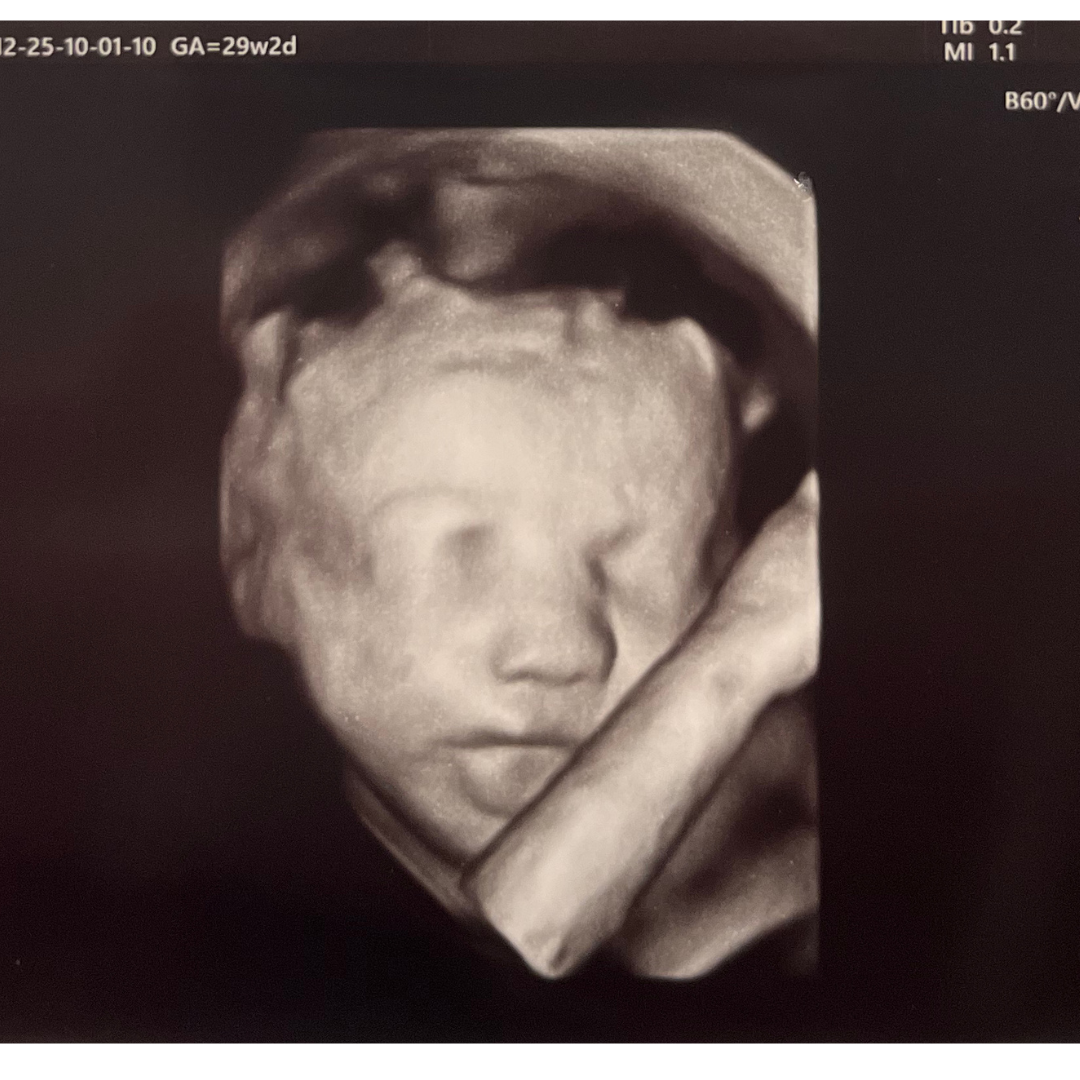

Ecografia 3D

L’ecografia 3D consente di ottenere delle immagini statiche, fisse: delle foto che riproducono le fattezze del feto. La procedura di acquisizione può essere talvolta macchinosa, perché l’acquisizione dei singoli fotogrammi va effettuata muovendo manualmente la sonda. L’ecografia 3D risulta quindi più dispendiosa, in termini di tempo, e può generare incertezza nei risultati: potrebbe essere necessario ripetere l’operazione più volte per ottenere immagini soddisfacenti.

Ecografia 4D

L’ecografia 4D, invece, permette di generare immagini tridimensionali in movimento ed in tempo reale, come se si utilizzasse una videocamera. Questa procedura prevede l’impiego di speciali sonde chiamate “volumetriche”, capaci di acquisire 25–30 fotogrammi al secondo senza movimento della sonda; ne consegue un’immediatezza nella visualizzazione dei particolari tridimensionali fetali.

In definitiva, quindi, l’ecografia 4D e 3D possono essere rispettivamente accostate al video e alla fotografia. La procedura è identica ad una classica ecografia e può essere effettuata sia per via transvaginale che per via sovrapubica. Può essere inoltre eseguita con successo e soddisfazione in qualsiasi periodo della gravidanza: il maggior impatto estetico si otterrà dalla 25.ma settimana in su, quando il feto ha raggiunto una certa dimensione.